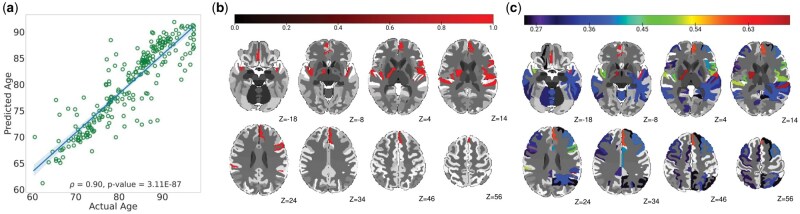

Age is a significant risk factor for mild cognitive impairment (MCI) and Alzheimer's disease (AD) and identifying brain age patterns is critical for comprehending the normal aging and MCI/AD processes. Prior studies have widely established the univariate relationships between brain regions and age, while multivariate associations remain largely unexplored. Herein, various artificial intelligence (AI) models were used to perform brain age prediction using an MRI dataset (n = 825). The optimal AI model was then integrated with the feature importance methods, namely Shapley additive explanations (SHAP), local interpretable model-agnostic explanations, and layer-wise relevance propagation, to identify the significant multivariate brain regions hierarchically involved in this prediction. Our results showed that the deep learning model (referred to as AgeNet) outperformed conventional machine learning models for brain age prediction, and that AgeNet integrated with SHAP (referred to as AgeNet-SHAP) identified all ground-truth perturbed regions as key predictors of brain age in semi-simulation, demonstrating the validity of our methodology. In the experimental dataset, when compared to cognitively normal (CN) participants, MCI exhibited moderate differences in brain regions, whereas AD showed highly robust and widely distributed regional differences. Individualized AgeNet-SHAP regional features further showed associations with clinical severity scores in the AD continuum. These results collectively facilitate data-driven explainable AI approaches for disease progression, diagnostics, prognostics, and personalized medicine efforts.